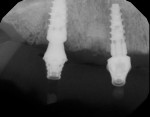

Once the implants had become integrated (Figure 9), they were uncovered in preparation for an implant level impression. Next, a clean impression was taken using vinyl polysiloxane (VPS) materials (Panasil®, Kettenbach), a stone cast was fabricated, and conventional bite relations and a wax setup were created. Denture teeth can be used to help determine the proper vertical dimension of occlusion and overall facial form (Figure 10 and Figure 11). After the patient is given an opportunity to evaluate the esthetics that were created and accept the position of the teeth, it is important to realize that any final prosthesis must be passively seated. Excessive forces cannot be placed upon the implants or abutment screws; therefore, another step was added to the process to improve the passivity of the appliance. Inlay resin jigs (DuraLay Inlay Pattern Resin, Reliance Dental Manufacturing) were created by the dental technician and independently threaded into each individual implant. After the jigs were luted together with a pattern resin (primopattern LC Gel, primotec USA) (Figure 12), a custom tray was filled with the appropriate impression materials, and a pickup impression of the screw-retained jigs was taken. This final impression needs to be very accurate because it will provide the laboratory technician with the best master cast to begin fabrication of the final prosthesis.

Once the master cast is fabricated, the dental laboratory technician will decide if multiunit abutments are needed to adjust the angulation of the retention screws through the access openings in the occlusal and palatal aspects of the prosthesis (Figure 13). If multiunit abutments are not chosen, then it may become necessary to place access holes in the facial aspect of the prosthesis, potentially creating an esthetic concern.

When the bite relation and final impressions were confirmed to be accurate, a polymethylmethacrylate (PMMA) appliance was fabricated (Figure 14). This transitional appliance can be easily modified for occlusal discrepancies and esthetic concerns. This modification process is continued until both form and function are appropriate. The patient may wear this PMMA try-in for 1 to 4 weeks to verify acceptance before the final prosthesis is fabricated. After any adjustments are made and the try-in appliance is finalized, it is returned to the laboratory. Using CAD/CAM, the final solid prosthesis was then milled from a zirconia puck (BruxZir®, Glidewell Laboratories). Figure 15 shows a side-by-side comparison of the PMMA try-in prosthesis and the final zirconia screw-retained prosthesis. Digital periapical radiographs of the multiunit abutments allowed the access holes to be placed on the palatal aspect of the final screw-retained prosthesis (Figure 16 and Figure 17).